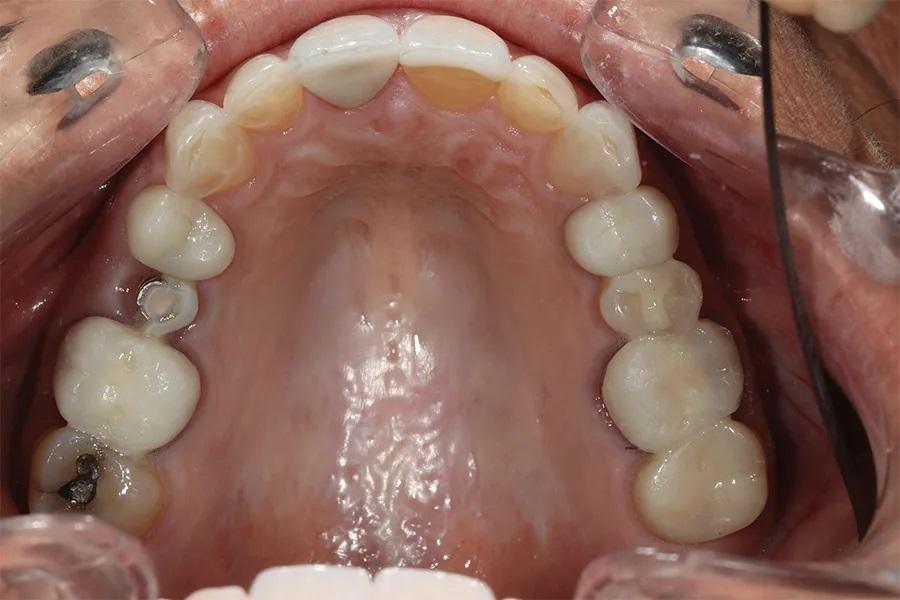

Фото 4. Окклюзионный вид верхней челюсти до лечения, демонстрирующий разрушенную временную конструкцию на имплантате в области зуба 15 и фрикционный износ на небной поверхности зубов 13–23.